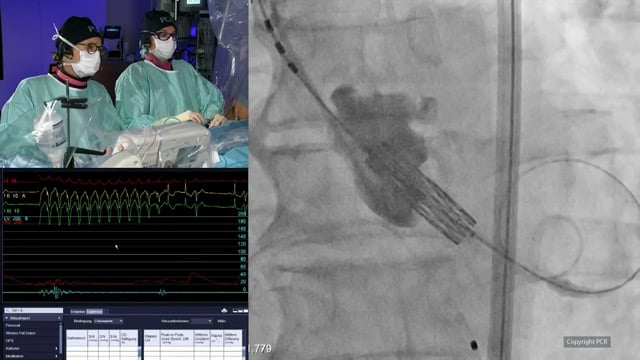

Performing BASILICA: a step-by-step guide to prevent coronary obstruction during TAVI

12 Sep 2025

Author